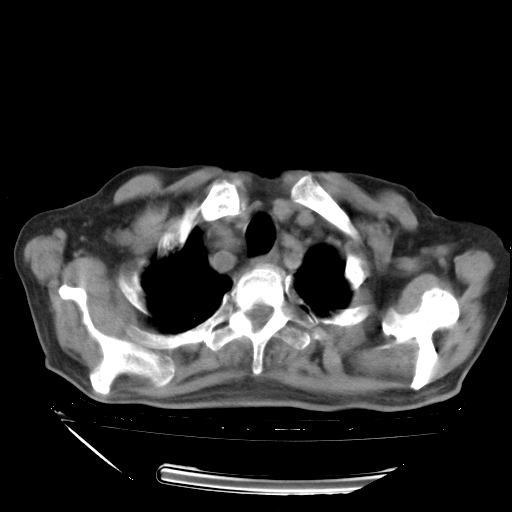

甲强龙80mg/日+抗结核治疗(异烟肼+利福霉素+乙胺丁醇)10天。复查肺部CT。

94186 2 1 .bmp

94186 3 1 .bmp

94186 3 2 .bmp

94186 3 3 .bmp

94186 3 4 .bmp

94186 3 5 .bmp

94186 3 6 .bmp

94186 3 7 .bmp

94186 3 8 .bmp

94186 3 9 .bmp